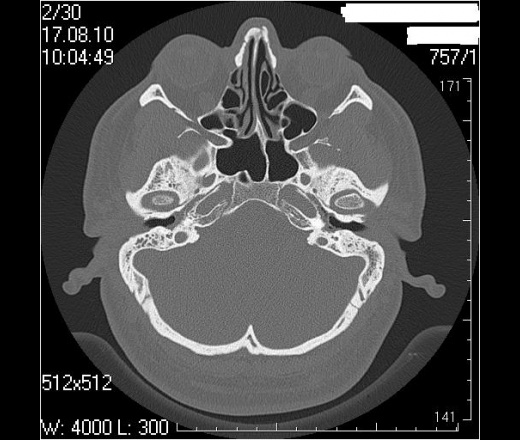

Сосцевидный отросток: тип строения склеротический, в сохранившихся ячейках отмечаются снижение прозрачности за счет патологических структур.

Воздушные полости среднего уха: пневматизация нарушена полностью за счет мягкотканных (41едН) патологических структур; размеры аттика, адитуса и антрума в пределах нормы. Ширина аттика ― 5,6мм (N=6.4-7мм), адитуса ― 2,1мм (N=3,1-3,3мм), антрума ― 4,6 мм.

Костное устье слуховой трубы: заполнено мягкотканными патологическими структурами.

Сосцевидный отросток: тип строения склеротический.

Воздушные полости среднего уха: пневматизация нарушена за счет пристеночных мягкотканных (41едН) патологических структур; размеры аттика, адитуса и антрума в пределах нормы. Ширина аттика (на уровне латерального канала) ― 5,7мм (N=6.4-7мм), адитуса ― 3,5мм (N=3,1-3,3мм), антрума ― 6,4мм.

Костное устье слуховой трубы: пристеночные мягкотканные патологические структуры.

Заключение: КТ- признаки двустороннего хронического среднего отита: склеротические изменения больше выражены в левом сосцевидном отростке; мягкотканные патологические структуры в воздушных полостях среднего уха больше выражены справа; блок костного устья правой слуховой трубы; неполный блок костного устья левой слуховой трубы

Соглашусь с Виталием. Мы делаем височные кости отдельными реконструкциями на правую и левую кость еще по 0,6мм. Здесь не знаю как, но вот по 0,6мм (кстати, так делают в Европе, насколько мне известно) плотность померить - результаты будут от фонаря. И еще мне режет уши - заполнено патологическими структурами. Что за структуры? Андрей Юрьевич, это Ваше описание? Я видел подобные в ММА Сеченова. вообще, мне нравится такой тип описания, когда все четко по полочкам разложено, не надо заниматься, порою, долгим поиском интересующей области в тексте описания. Кстати, достоверного блока устья левой трубы не вижу на представленных томограммах. Похоже, просто не те срезы выбраны. (сразу скажу, я не спец по ушам , хочется разобраться) Вернее сказать, вообще не вижу блоков. Покажите, если не трудно

Андрей Юрьевич, про размеры... Пишите, что размеры в пределах нормы, затем указываете параметр и норму, в которую этот параметр не укладывается. Или я что-то не так понял?

А засада (что НЕ ТАК), для меня здесь вот в чем. У пациента клиника левостороннего отита (многолетний анамнез, отделяемое из уха, перфорация перепонной барабанки при отоскопии), а справа клиники нет совсем. После КТ ЛОРы дописали рубец на правой перепонке, и выписали + с адгезивныи отитом справа (хотя при адгезивном отите КТ-картина должна быть несколько иная).

А сижу и думаю, чтож это было-то, и правильные ли я сделал выводы? Или тут тоже действует этот радиологический перл : Sinusitis is a clinical diagnosis. Sinus images frequently bear no relationship to the patient's symptoms. - Синусит-это клинический диагноз. То что мы иногда видим в синусах, зачастую не имеет никакого отношения к симптомам которые испытывает исследуемый нами пациент. Richard H. Daffner MD, FACR. Professor of Radiologic Sciences. Clinical Radiology.